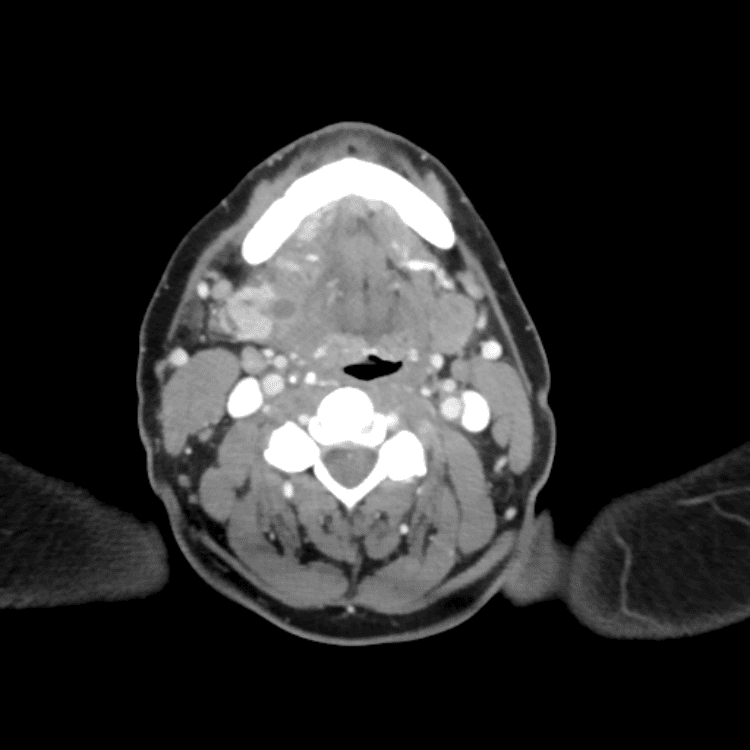

Head and Neck

Practice

Simulates call by including subtle or difficult cases and some normals.

27 cases